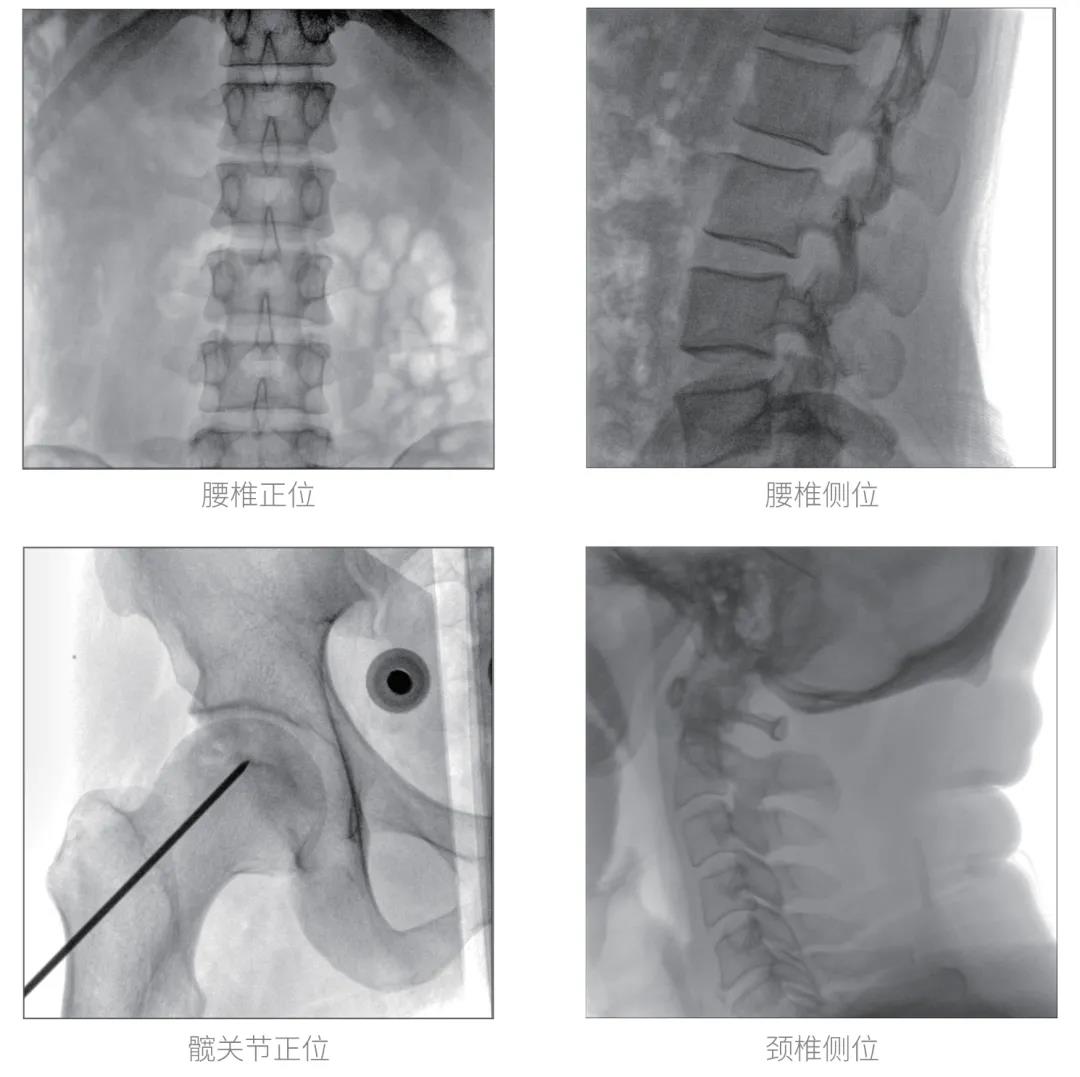

經(jīng)過認(rèn)真詳盡的設(shè)備審核驗(yàn)收,“慧瞳”正式投入使用,普愛醫(yī)療一體化平板C形臂采取的動(dòng)態(tài)平板探測(cè)器和智能圖像處理技術(shù),讓臨床圖像更加清晰。

普愛醫(yī)療一體化平板C形臂“慧瞳”采用小巧緊湊的一體化機(jī)架設(shè)計(jì),配合高性能的動(dòng)態(tài)平板探測(cè)器,移動(dòng)靈活,成像清晰,是各級(jí)醫(yī)院開展骨科及其相關(guān)外科手術(shù)的科室使用的理想設(shè)備。

智能化實(shí)時(shí)圖像處理技術(shù),自動(dòng)分析圖像并進(jìn)行增強(qiáng)處理,減少臨床應(yīng)用中處理圖像時(shí)的繁瑣操作,快速提供優(yōu)質(zhì)圖像方便完成臨床工作。